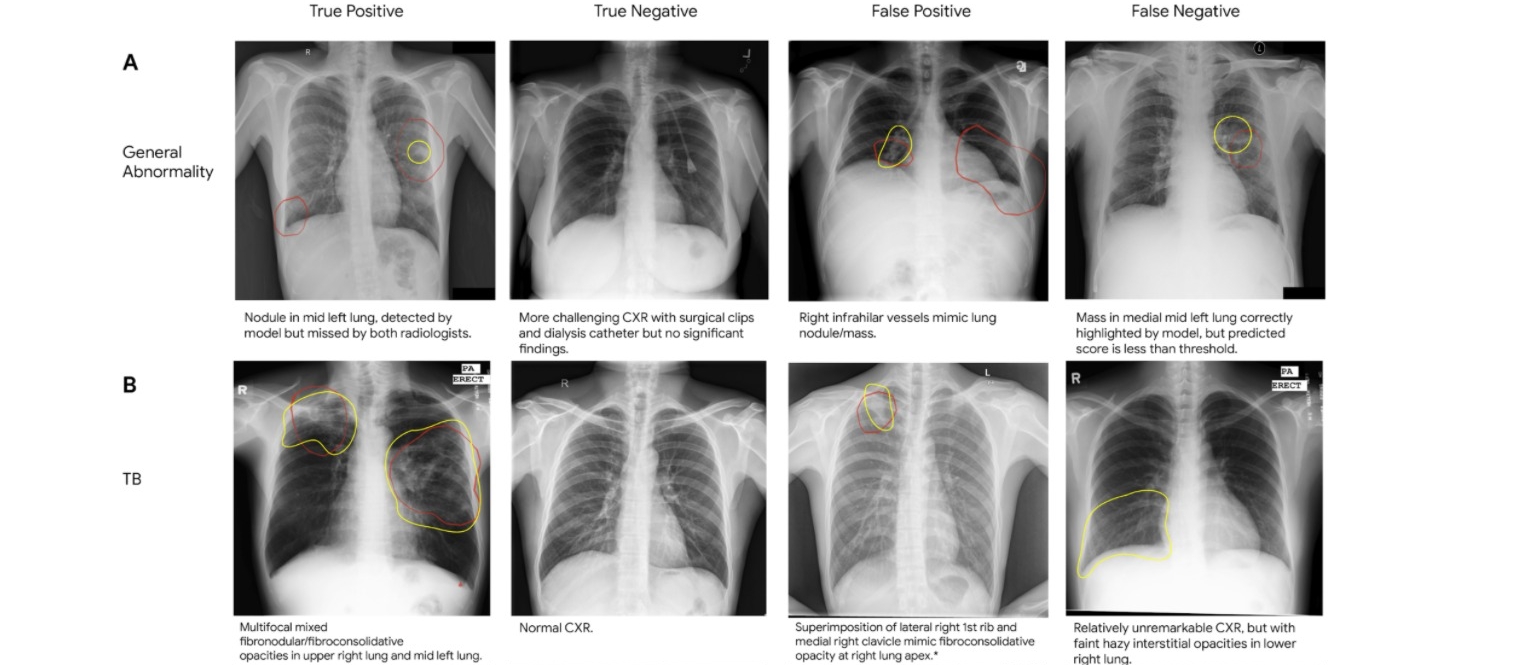

该数据集被精心组织成三个文件夹:训练、测试和验证。每个文件夹包含每个图像类别的子文件夹,即肺炎和正常。该数据集包含 5,863 张 X 射线图像(JPEG 格式),分为两个类别(肺炎/正常)。 胸部 X 射线图像(前后位)选自广州市妇女儿童医疗中心 1 至 5 岁儿童患者的回顾性队列。所有胸部 X 射线成像均作为患者常规临床护理的一部分进行。 为了分析胸部 X 射线图像,首先通过删除所有低质量或不可读的扫描来筛选所有胸部 X 射线照片以进行质量控制。然后,两位专家医生对图像的诊断进行了分级,然后才允许训练人工智能系统。为了解决任何评分错误,评估集还由第三位专家进行了检查。